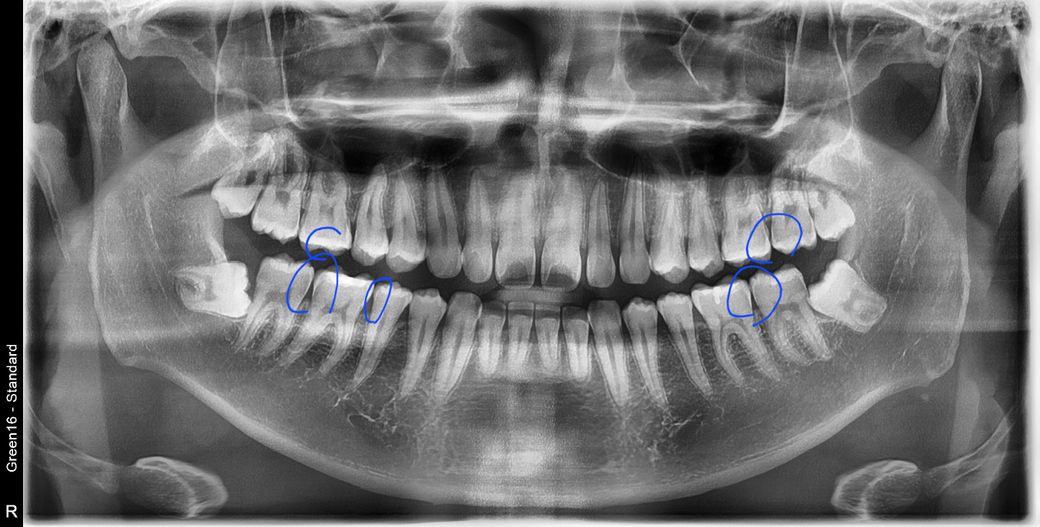

사진속 구강상태에서 초기 정지우식이라고합니다. 근데 재광화가풀려 며칠동안 조금이라도 정지우식이 다시 진행되었다면, 진행된지 고작 2주정도 지났다고 쳐도 인레이가 필요한치아가 있나요? 많이 진행되지않고 2주동안 이제막 충치가번지기 시작하는경우, 레진인지 인레이인지 궁금합니다

• 3번 째 사진

충치가 진행이 되는 것이 치아 사이의 경우에는 보통 레진보다는 인레이로 치료하는 것이 일반적입니다.

충치의 범위가 넓거나 인접면에 충치가 있는 경우에는 보철치료를 하게 됩니다.

범위가 넓지 않다면 인레이 치료를 할수 있지만 범위가 넓다면 크라운 치료가 필요할 수 있습니다.